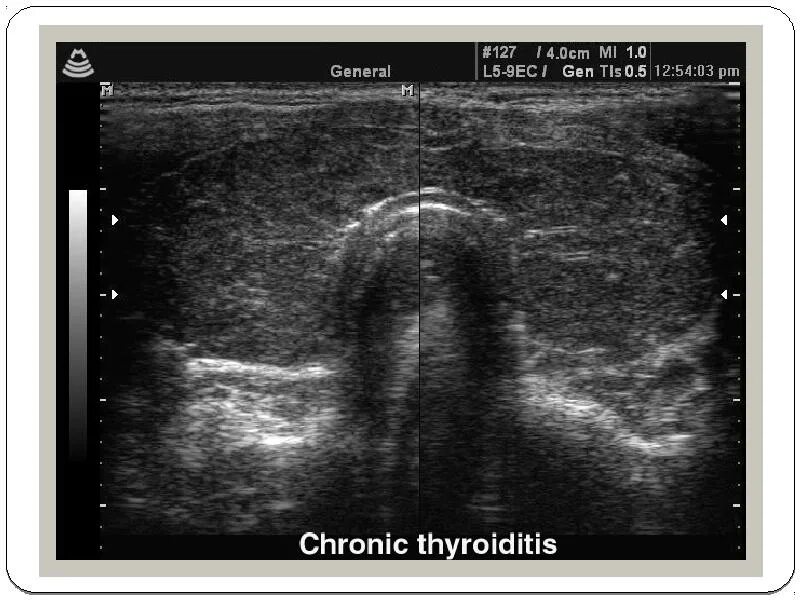

Диффузные изменения щитовидной железы на узи